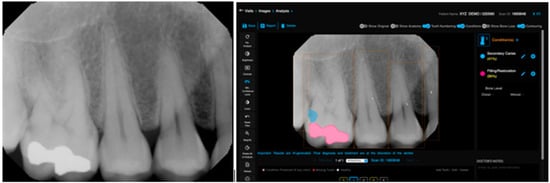

Figure 2.

Teeth numbering, caries, and restoration detection on a periapical radiograph using the deep learning algorithm.